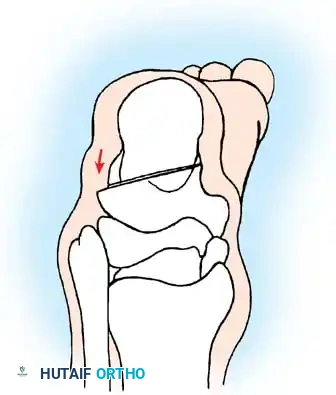

تشوهات القدم في الشلل الدماغي هي حالة شائعة ناتجة عن التشنج العضلي المستمر، وأبرزها القدم الخيلية أو المشي على أطراف الأصابع. يبدأ العلاج بالطرق التحفظية مثل الجبائر وحقن البوتكس، وقد يتطلب تدخلاً جراحياً دقيقاً لتطويل الأوتار وتصحيح العظام لضمان قدرة الطفل على المشي بشكل طبيعي ومستقل.

الخلاصة الطبية السريعة: تشوهات القدم في الشلل الدماغي هي حالة شائعة ناتجة عن التشنج العضلي المستمر، وأبرزها القدم الخيلية أو المشي على أطراف الأصابع. يبدأ العلاج بالطرق التحفظية مثل الجبائر وحقن البوتكس، وقد يتطلب تدخلاً جراحياً دقيقاً لتطويل الأوتار وتصحيح العظام لضمان قدرة الطفل على المشي بشكل طبيعي ومستقل.